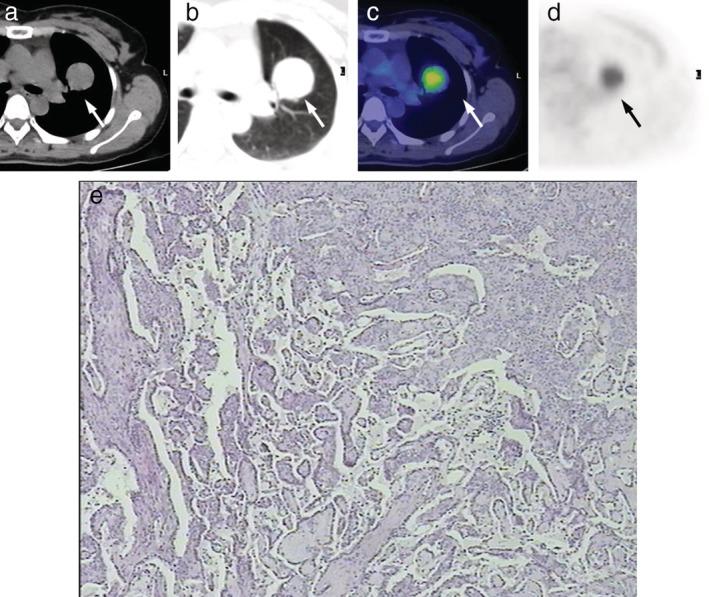

We sought to investigate the clinical features and F-FDG PET/CT characteristics of pulmonary sclerosing pneumocytoma (PSP).

We retrospectively reviewed and comparatively analyzed F-FDG PET/CT imaging results of 22 patients with diagnosed PSP in our hospital from November 2009 to September 2015.

The SUV in tumors was positively correlated with tumor size in typical PSPs (R = 0.806, R = 0.650, P = 0.001); however, the SUV in tumors had no significant correlation with tumor size of atypical PSPs (R = 0.479, R = 0.229, P = 0.162), and the degree of correlation between them attenuated when atypical PSPs were included (R = 0.518, R = 0.268, P = 0.011). A majority (90%) of atypical PSPs were found in males. Symptomatic patients showed a higher SUV than the asymptomatic group (5.68 ± 3.63 vs. 2.76 ± 1.18, respectively, P = 0.002).

Tumor size and clinical features may be associated with increased FDG uptake in PSPs. Morphological differences may affect the correlation between tumor size and SUV in PSPs. The atypical form of PSP may be more common in men.